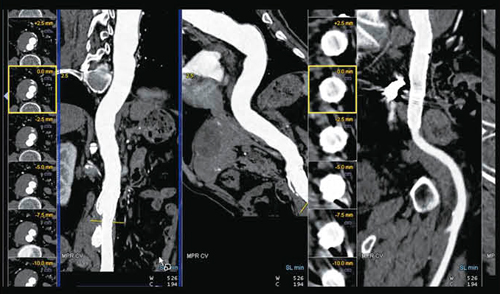

読影フローとしてまず,CT Vascular Analysisによって血管系の評価を行っているが,頸動脈,腎動脈,ステントなどの血管がすでに選択された状態で画面が立ち上がり,それぞれの血管の様子がスムーズに確認できる(図3)。この症例では,run-offやステントの状態も良好に描出されている。ただ,詳細に見ると下腸間膜動脈を介するtypeⅡのエンドリークが認められた(図4)。同時に,肺野の評価は,MM OncologyのCT Lung Careで行ったが,こちらも画面を起動すると,すでに肺野の結節が自動的に拾い上げられており,肺野の転移性病変についても,短時間で読影が行える(図5)。

図3 syngo CT Vascular Analysisによる血管解析とsyngo CT Lung CARE

主要血管の状態を直ちに確認することができる。

図4 syngo CT Vascular Analysisによる血管解析とsyngo CT Lung CARE

typeⅡのエンドリークが認められる。